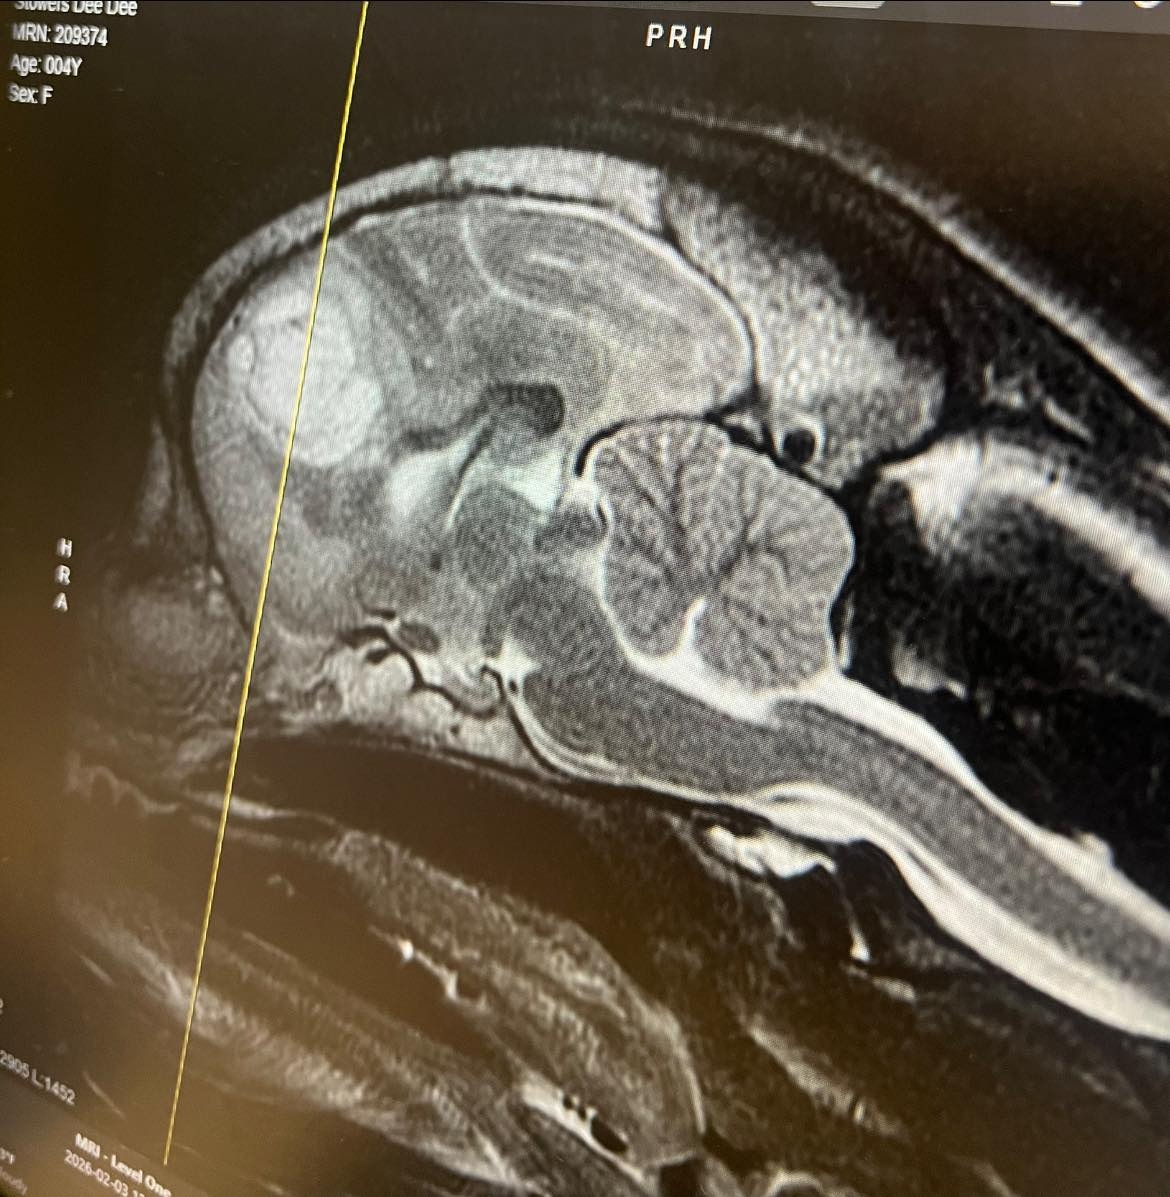

On Monday, February 2nd, my sweet girl Didi began having uncontrollable seizures. The first one lasted nearly an hour, and even with medication, they continued throughout the night. After a long and terrifying night in the ER, followed by a visit to the neurologist, we received devastating news — Didi has a brain tumor.

She is now on seizure medications and steroids as we prepare for Stereotactic Radiotherapy (SRT) Radiation Therapy in March. This treatment gives us the best chance at more comfortable, precious time together, and I am committed to doing everything in my power for her.